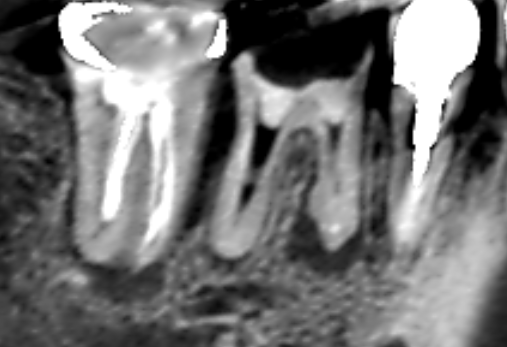

初診時の下顎第一大臼歯と第二大臼歯の矢状断のCT画像です。

赤い矢印の先の下顎第一大臼歯の近心根の根の先に膿の影がみられます。

下顎第二大臼歯の近心根の近心側に歯槽骨の吸収による長い影がみられます。歯根破折が疑えます。